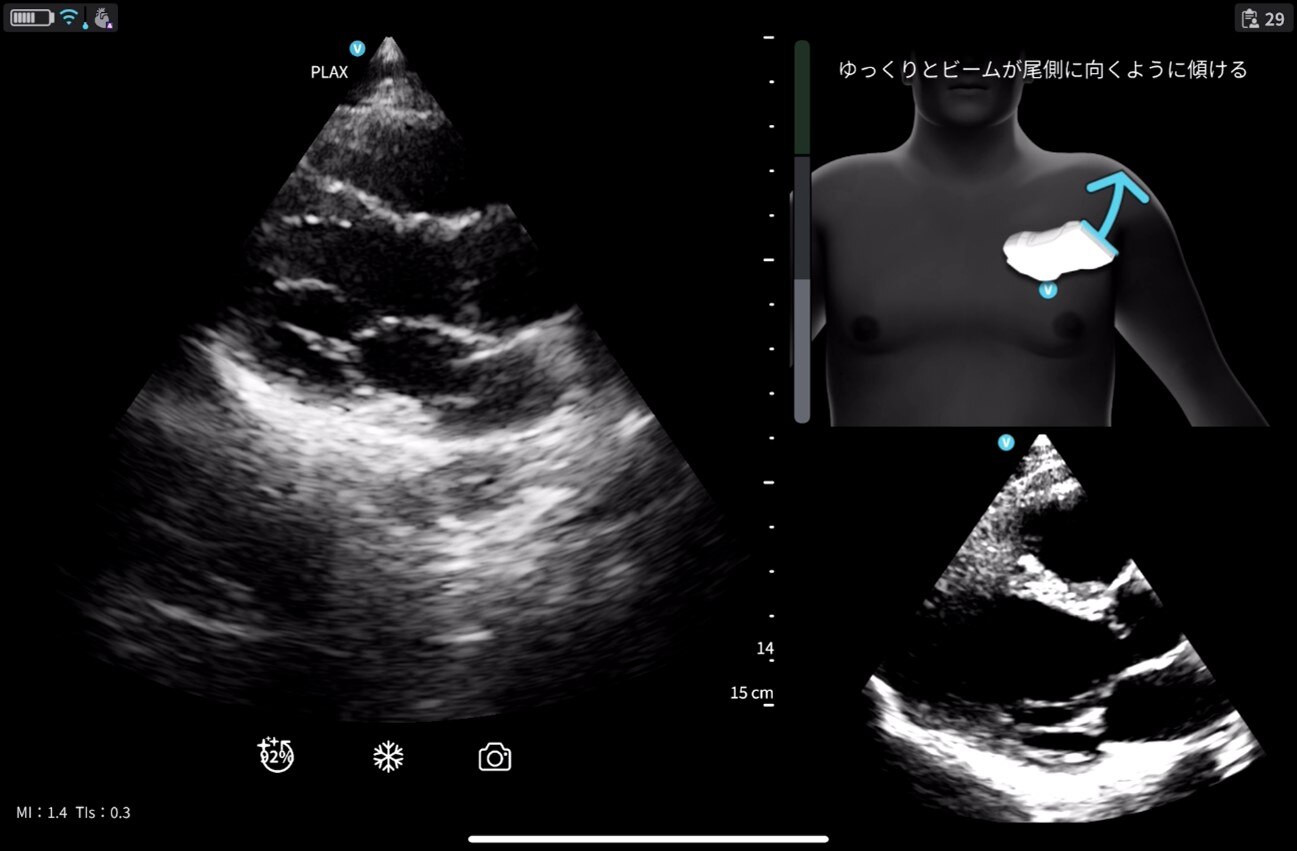

※Cardiac Guidance/ Interpretationの実際の画面

※Cardiac Guidanceによる心エコー検査のリアルタイムガイド表示機能。

Quality Meterで画像クオリティを確認、画面上部にはイラストとともに「時計回りにゆっくりと回転」などリアルタイムに様々なガイダンスが表示されます。